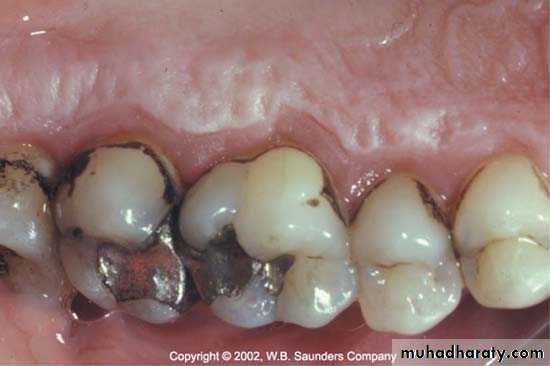

Food ImpactionIt is the forceful wedging of food into the periodontium by occlusal forces.

The factors leading to food impaction:-

-Uneven occlusal wear.

-Opening of the contact point as a result of loss of proximal support or from extrusion.

-Congenital morphologic abnormalities.

-Improperly constructed restorations.

Forceful wedging of food into periodontium by occlusal force can leads to gingival inflammation & delay of periodental treatment.

Plunger cusp; cusp that tend to forcibly wedge food interproximally ,occur due to wear or shift in tooth positionFood impaction